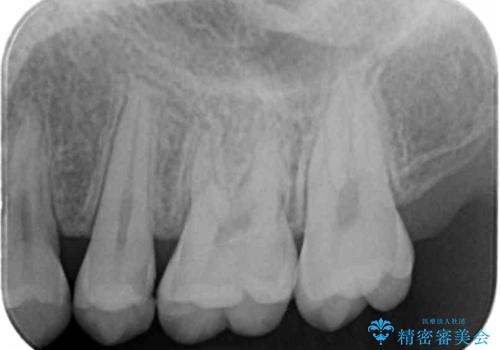

- 検査の結果虫歯が見つかった患者様です。

レントゲン画像と視診から詰め物で対応可能と判断したためインレーでの修復をしていきます。